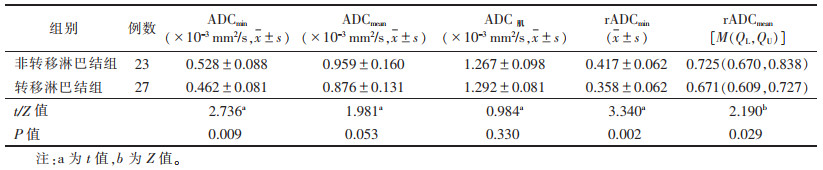

2.2 2组ADC值比较(表 1)| 表 1 直肠腺癌非转移淋巴结组与转移淋巴结组的ADC值比较 |

转移淋巴结组ADCmin、ADCmean、rADCmin、rADCmean值均较非转移淋巴结组小,其中ADCmin、rADCmin、rADCmean值差异均有统计学意义(均P<0.05),ADCmean、ADC肌值差异均无统计学意义(均P > 0.05)(图 1,2)。